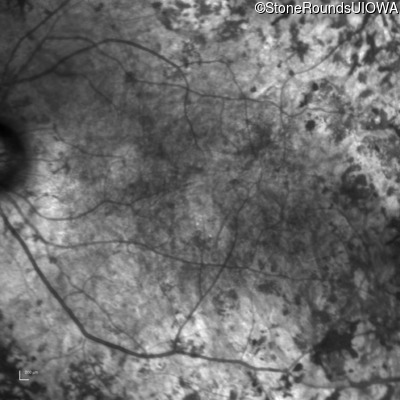

Infrared Fundus Photograph - Left - Light Perception

Exemplar